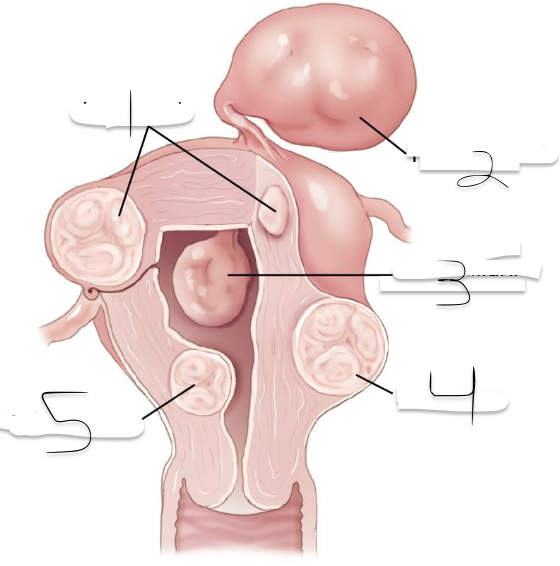

1?

Intramural

2?

Pedunculated

3?

Intracavitary

4?

Suberous

5?

Submuscosal